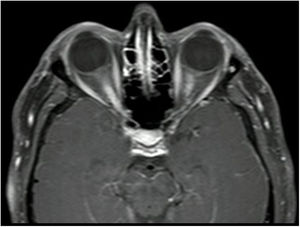

Neuritis óptica (figs. 2 y 3), que suele ser extensa, con compromiso del quiasma óptico o más del 50% de la longitud del nervio óptico y con un compromiso de moderado a severo de la agudeza visual.

Las lesiones medulares por NMO son longitudinalmente extensas, es decir, comprometen tres o más segmentos medulares contiguos, y transversas o centromedulares, por lo que generan paraparesia o cuadriparesia asociada con síndromes sensitivos medulares, según el nivel de la lesión28.